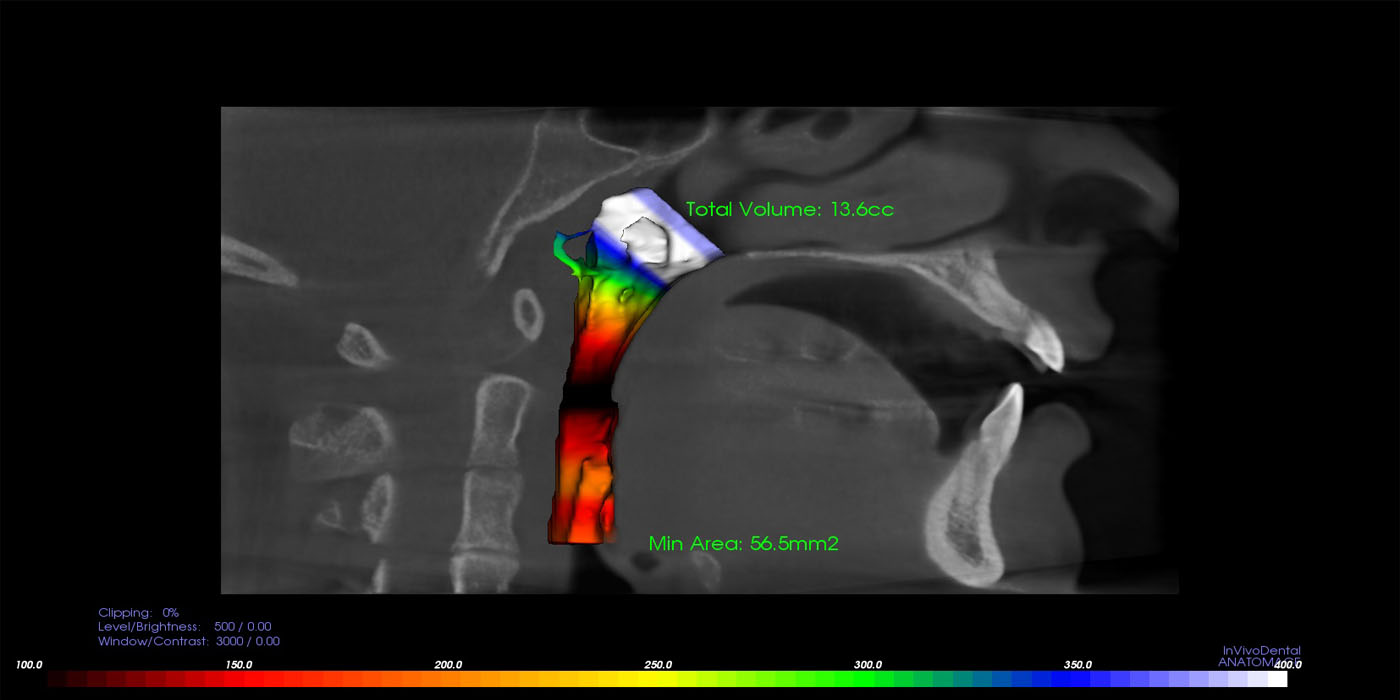

Airway Scan

The upper airway is an extraordinarily complex anatomic region that may be affected by various disease states. The upper airway includes the nose, nasopharynx, oropharynx, hypopharynx, larynx, and trachea, and these structures may be involved by both focal and diffuse processes.

There are also many adjacent bony and soft tissue structures that are no less complex in their anatomic arrangement. Lesions in these regions can cause extrinsic compression resulting in a compromised airway. This scan will provide with detailed evaluation of the area and its diagnosis for various problems.